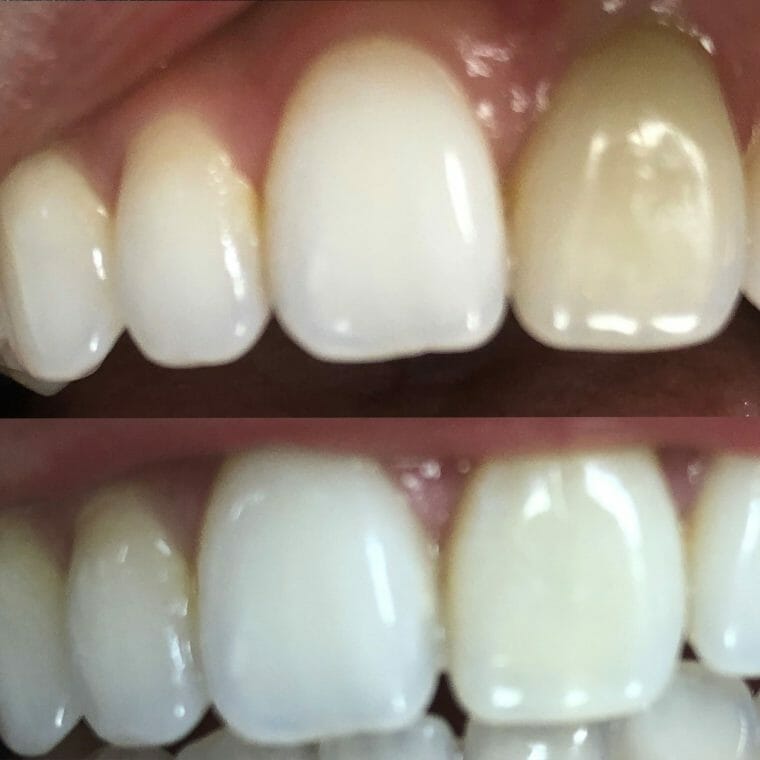

Internal Bleaching

Case Studies/